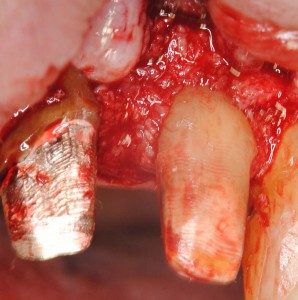

久しぶりの再生療法。歯周病で歯の周りの骨が溶けてしまった部位に、骨誘導材料を置いて失われた組織の再生を図るというもの。歯周治療の最前線治療を行っている指導医からもらったアドバイスを念頭におきながら、慎重に行った。夜はペントロンというメーカーの歯科用マイクロスコープを大井町にあるショールームに見に行った。マイクロスコープをここぞという時に使えるのは来年か?年をとっても、これさえあれば若いドクターに負けないという(目の衰えという点で)話を聞いたことがある。マイクロスコープ関連のセミナーに参加したいが、医科歯科大学インプラント治療部出身のK先生に聞いてみるとしよう。患者さんからいただいた(というより預かった)金で、新しい投資をし、患者さんに還元する。このサイクルが失われたら、私も終わり(長谷川)。

歯周病と歯周組織再生療法